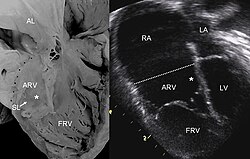

![]() YSM-də Ebşteyn anomaliyasının təsviri. | |

Bu zaman üçtaylı qapağın arxa və arakəsmə qapaqcığı müxtəlif dərəcədə aşağı sürüşmüş ya düşmüş olaraq mədəcik divarına pərçimlənmiş və sağ mədəciyin proksimal hissəsi nazik, məməyəbənzər əzələ və xordalar deformasiyalaşmış olur. Çox vaxt dartılmış açıq qalmış oval dəlik vasitəsilə qulaqcıqlarla rabitədə olur.